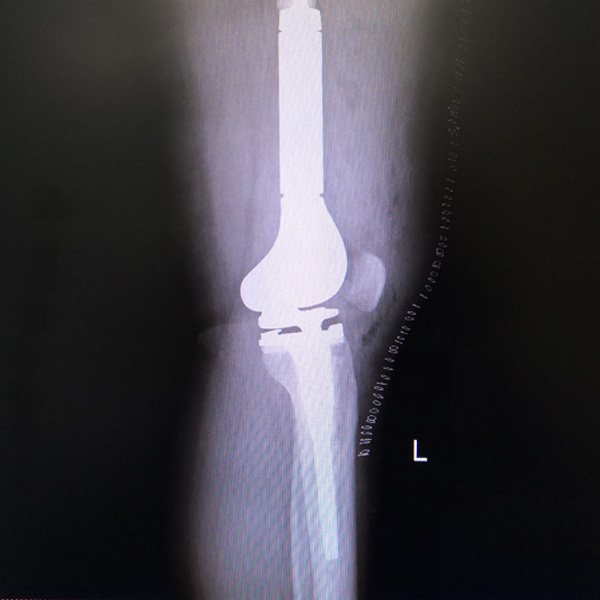

骨肉瘤手術

患者張某,女,14歲,診斷為“左股骨遠端骨肉瘤”,當?shù)蒯t(yī)院因為醫(yī)療技術和能力的限制,只能考慮截肢手術。患者家屬通過平臺推薦,指定到哈......